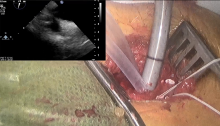

Pictured: The Altmetric badge for “Isolated Endoscopic Tricuspid Valve Surgery”

- Isolated Endoscopic Tricuspid Valve Surgery [3]